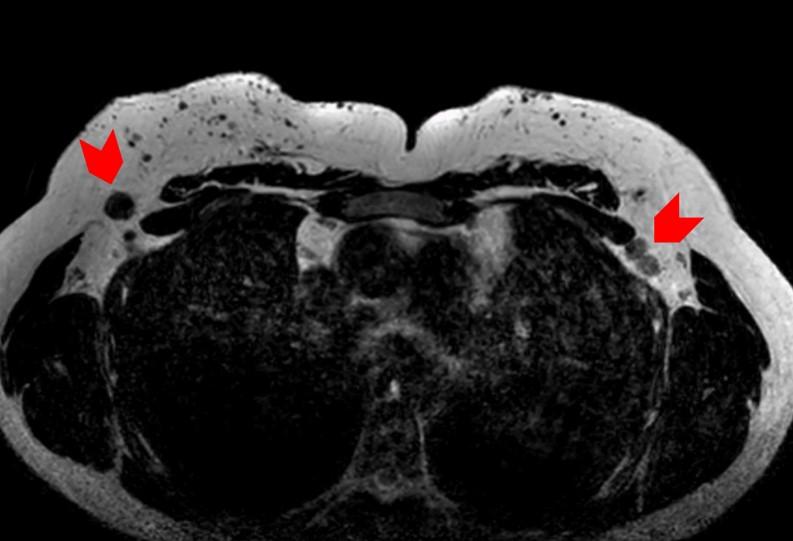

腋下MR影像显示双侧呈球形肿块,在T1WI上表现为低信号。在T1WI对比增强脂肪饱和影像中,可见腋下肿块呈异质性明显强化,伴有点状脂肪区域(图6、7)。